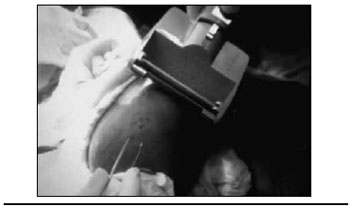

Realizou-se tricotomia do couro cabeludo, antissepsia local e infiltraçao apenas com soro fisiológico 0,9%, para criar edema local e facilitar a retirada do enxerto (Figura 3). Após o preparo da área, foram retirados os enxertos de couro cabeludo com o uso do dermátomo (Figuras 4 e 5).

Figura 3 - Intumescimento do couro cabeludo.

Figura 4 - Retirada do enxerto cutâneo com dermátomo.